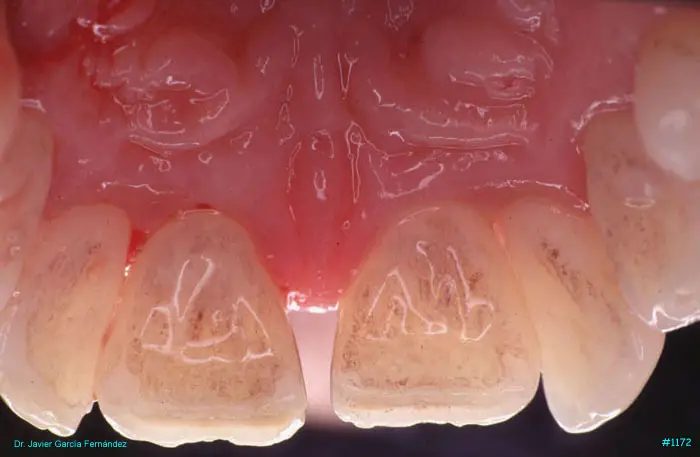

Atlas of Surgical Techniques in Periodontics. Chapter III. Atlas de Técnicas Quirúrgicas en Periodoncia